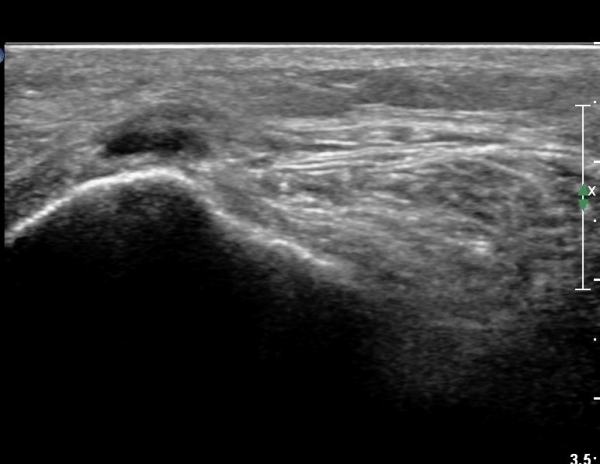

ŽÃËÀÚ¸¦ ¸»´ÜÀ¸·Î À̵¿ÇÏ´Ï À̵ιڱ٠³»Ãø¿¡¼­ ºñ°ñ½Å°æ¿Í °üÂûµÈ´Ù(»çÁø 2).